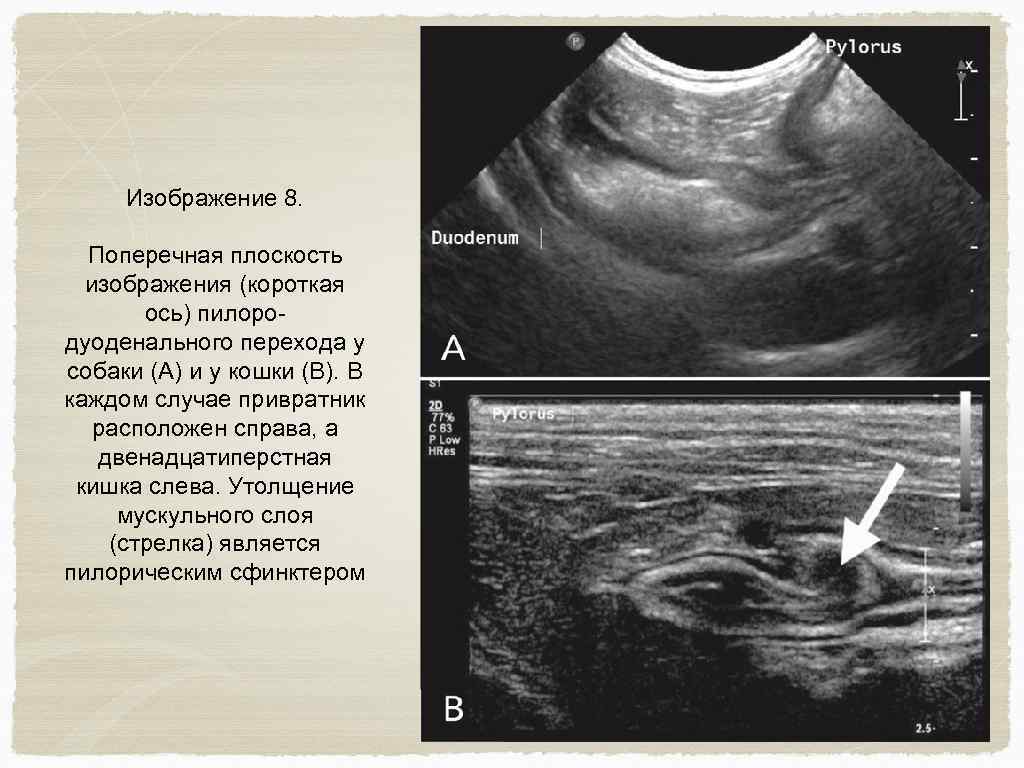

Желудочно-кишечный тракт и поджелудочная железа Исследование проводится в среднем отделе брюшной полости ; установите датчик по длинной оси каудально к печени, так чтобы была видна поперечная проекция желудка. Сдвиньте датчик каудально для определения ободочной кишки в поперечной плоскости (изображение 6) Левая доля поджелудочной железы расположена между желудком и ободочной кишкой, прилегает к селезеночной вене, которая пересекает брюшную полость слева на право и формирует воротную вену. (изображение 7) Вращайте датчик в поперечной плоскости и двигайте его вдоль правой стороны желудка в пилоро-дуоденальное соединение. (изображение 8) Вместе с датчиком, лежащим в поперечной плоскости (с пометкой правой стороны пациента) , следуйте дистально двенадцатиперстной кишки

Изображение 8. Поперечная плоскость изображения (короткая ось) пилородуоденального перехода у собаки (А) и у кошки (В). В каждом случае привратник расположен справа, а двенадцатиперстная кишка слева. Утолщение мускульного слоя (стрелка) является пилорическим сфинктером